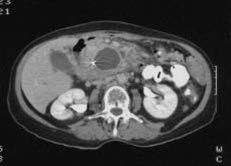

CT bilder er svarthvite. Organene fremstilles i ulike grader av grått. Vev med lav tetthet, f.eks. luftfylte hulrom, vises som mørke eller svarte partier. Vev med høyere tetthet vises i lysere gråtoner. Jo høyere tetthet, jo lysere. Beinvev fremstilles hvitt.

Pseudocyste i bukspyttkjertelenSiden CT kan skille mellom ulike indre organ, såkalte bløtdeler, så kan CT av bukhulen gi detaljerte tverrsnittsbilder av organene i bukhulen, f.eks. leveren og galleveiene, milten, bukspyttkjertelen, nyrer og urinveier. Bildene fremstår i ulike nyanser av grått. Jo lysere skygge, jo høyere tetthet har vevet eller strukturen. Bein fremstilles hvitt, mens luft fremstilles sort. Bildeinformasjonen kan forbedres ved samtidig bruk av kontrastinjeksjon.